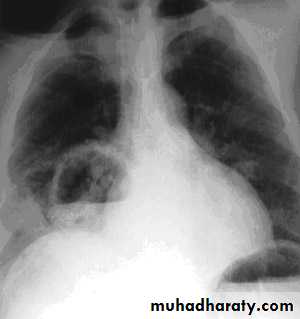

Bronchopneumonia

Breathlessness and central cyanosis

Pleural pain is uncommon

Chest X-ray shows mottled opacities in both lung fields, chiefly in the lower zones.